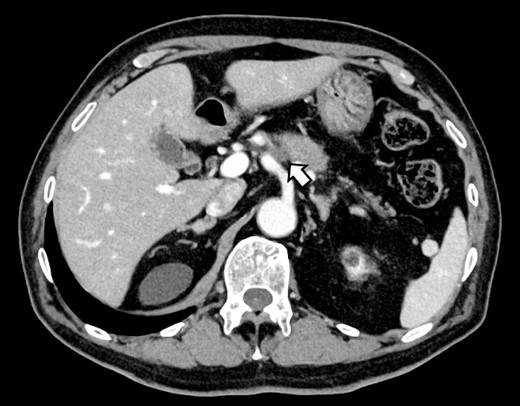

CT on postoperative Day 61. Although blood flow in the PHA could not be confirmed (arrow), the right and left hepatic arteries are preserved.

Subsequently, interventional radiology (IVR) was performed. However, because the inferior pancreaticoduodenal artery (IPDA) was very narrow, the microcatheter could not be followed, and hemostasis with IVR was difficult. Therefore, on POD 48, relaparotomy pseudoaneurysm repair was performed. The abdomen was opened through an inverted L-shaped incision, and adhesiolysis was performed, after which a pseudoaneurysm was revealed at the junction of the GDA and PHA. Four transfixing sutures with 3–0 prolene were used. After confirming that the liver blood flow was maintained, surgery was completed. However, bloody drainage from the drain was observed on POD 56. CeCT revealed a pseudoaneurysm (Fig. 3A and B). IVR was considered difficult because of the narrow blood vessels; therefore, the patient underwent a second laparotomy for hemostasis. A pseudoaneurysm was further observed at the junction between the GDA and PHA. In this operation, we used deeper and wider penetrating sutures than in the previous surgery to completely halt blood flow in the GDA. We confirmed that the blood flow to the liver was maintained; however, it was deemed weak. The patient had an uneventful postoperative course without bleeding, and CeCT performed on POD 61 confirmed the disappearance of the pseudoaneurysm. Although the blood flow in the PHA could not be confirmed, the right and left hepatic arteries were preserved (Fig. 4). On POD 76, CT revealed no liver abscesses or infarctions. The drain was removed on POD 78, and the patient was finally discharged on POD 107 without rebleeding or liver failure.

In this case, relaparotomy repair was performed for a pseudoaneurysm at the junction of the GDA and PHA. Preoperative CT showed no vascular variations. CeCT on POD 56 confirmed blood flow in the left and right hepatic arteries but not in the PHA. The CHA provides the main blood supply to the liver; however, the right and left accessory hepatic arteries and the inferior phrenic artery also play a role. Therefore, recent studies suggest that the CHA is not essential for parenchymal survival [10]. Collateral vessels are identified 4 h after vascular ligation and increase in size and number over the next 6 months [11]. Therefore, we speculate that collateral blood channels from the inferior phrenic artery and vessels of the lesser diaphragm had developed and hepatic blood flow was preserved in our case. In a search of the literature, we did not find any cases in which hemostasis was performed for a pseudoaneurysm at the junction of the GDA and PHA and hepatic blood flow was maintained by collateral blood vessels in a patient without a vascular anomaly, as in the present case. This suggests that IVR remains the best technique to achieve hemostasis for pseudoaneurysms, but, even when hemostasis by IVR is difficult, following some postoperative days, collateral vessels develop, and hepatic blood flow may be maintained even after relaparotomy pseudoaneurysm repair. Re-relaparotomy pseudoaneurysm repair after DP-CAR may be useful after some postoperative.